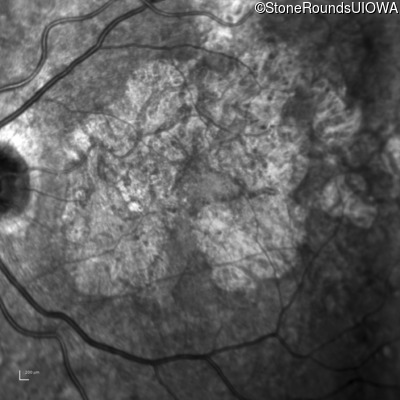

AR Stargardt Disease (IIA)

Age at visit: 56 years

This 56 year old man underwent surgery for strabismus in early childhood. He felt that his vision was good for most of his life, but about 5 years ago he first experienced difficulty following a golf ball in flight.

Diagnosis & molecular findings

Disease Gene Allele 1 variant(s) Allele 2 variant(s) Inheritance mode

AR Stargardt Disease ABCA4 Asn965Ser AAT>AGT Glu2131Lys GAA>AAA AR